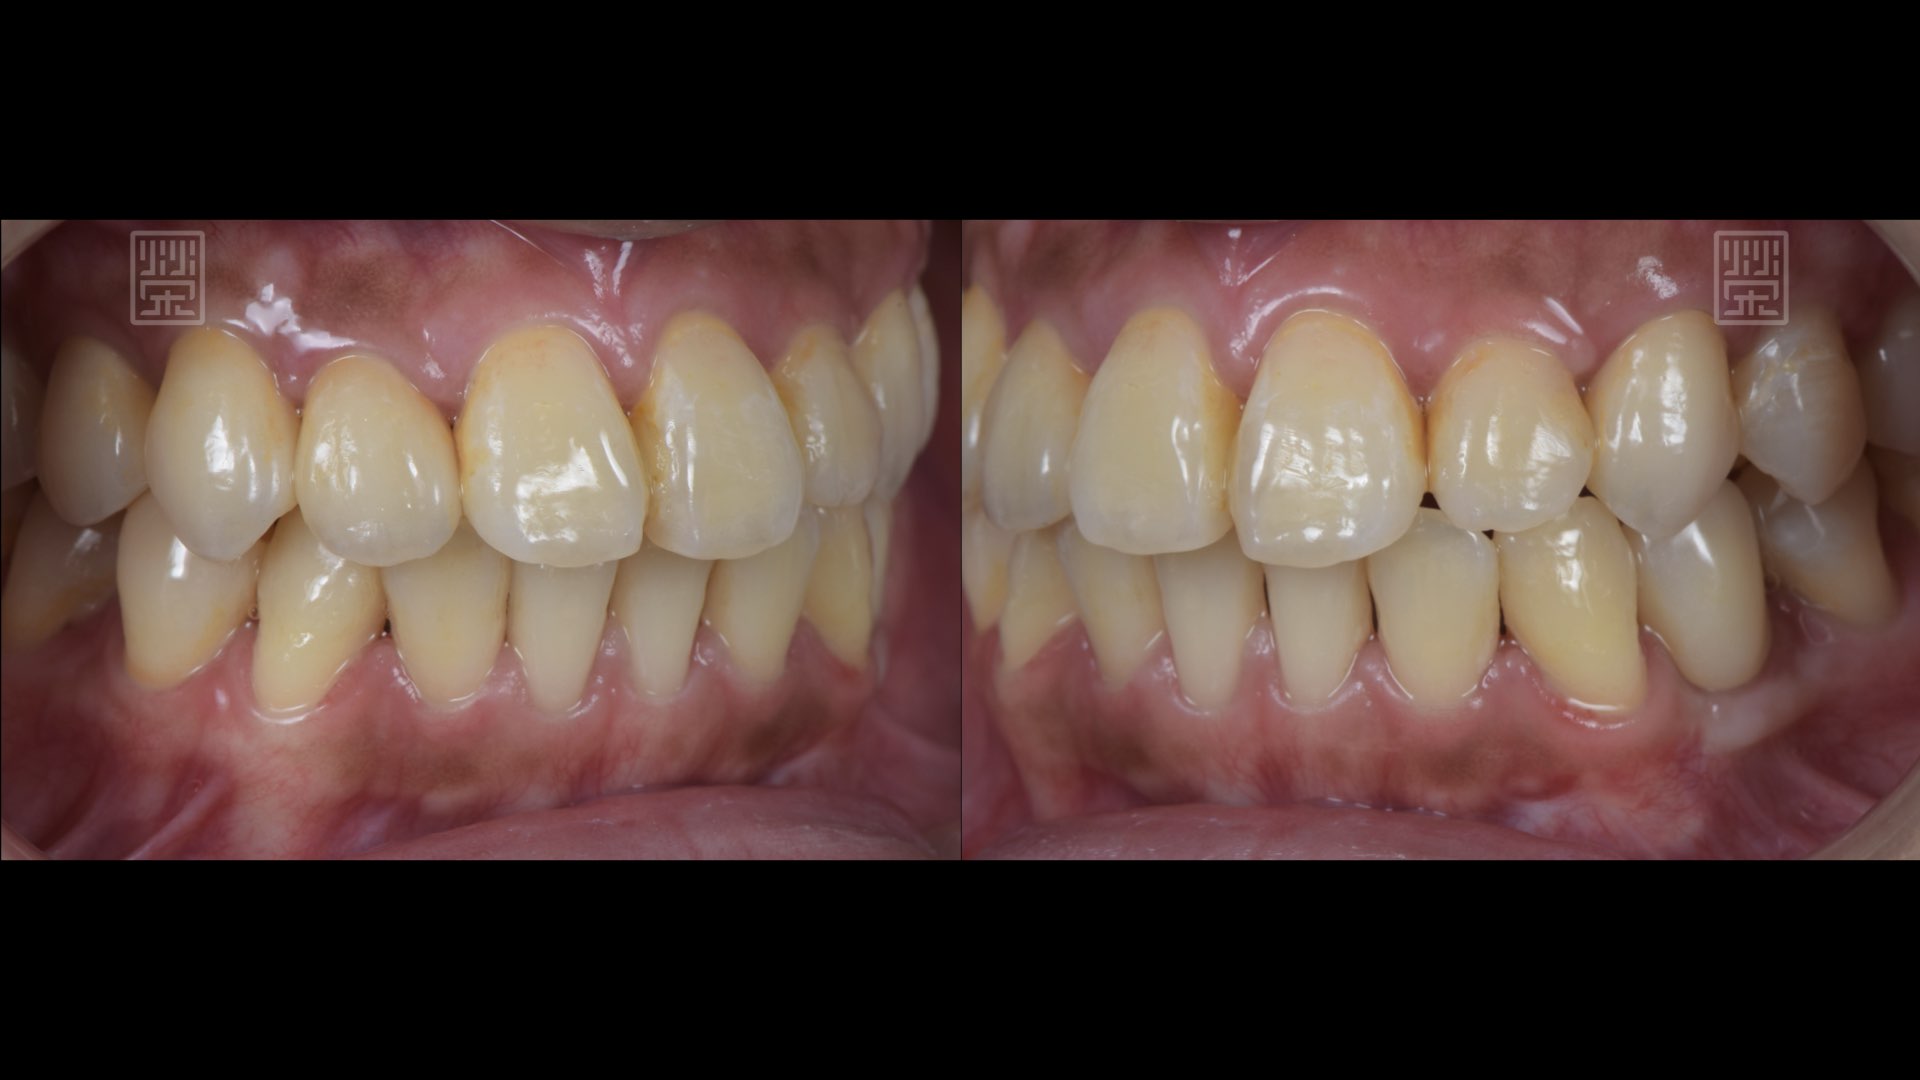

全瓷冠、植牙修復完成